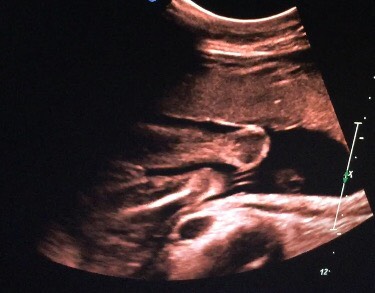

Девочка!!! Нам сказали, что у нас будет дочечка!!! Аааа!!! Мы такие счастливые!😍👏🎊🎉 после долгих уговоров китайские врачи раскололись. Они боялись, что мы хотим мальчика. В Китае почти каждая семья первым делом хочет родить мальчика. Многие делают аборты, если девочка. Поэтому им запрещено вообще сообщать кто. Но у нас везде есть друзья😏